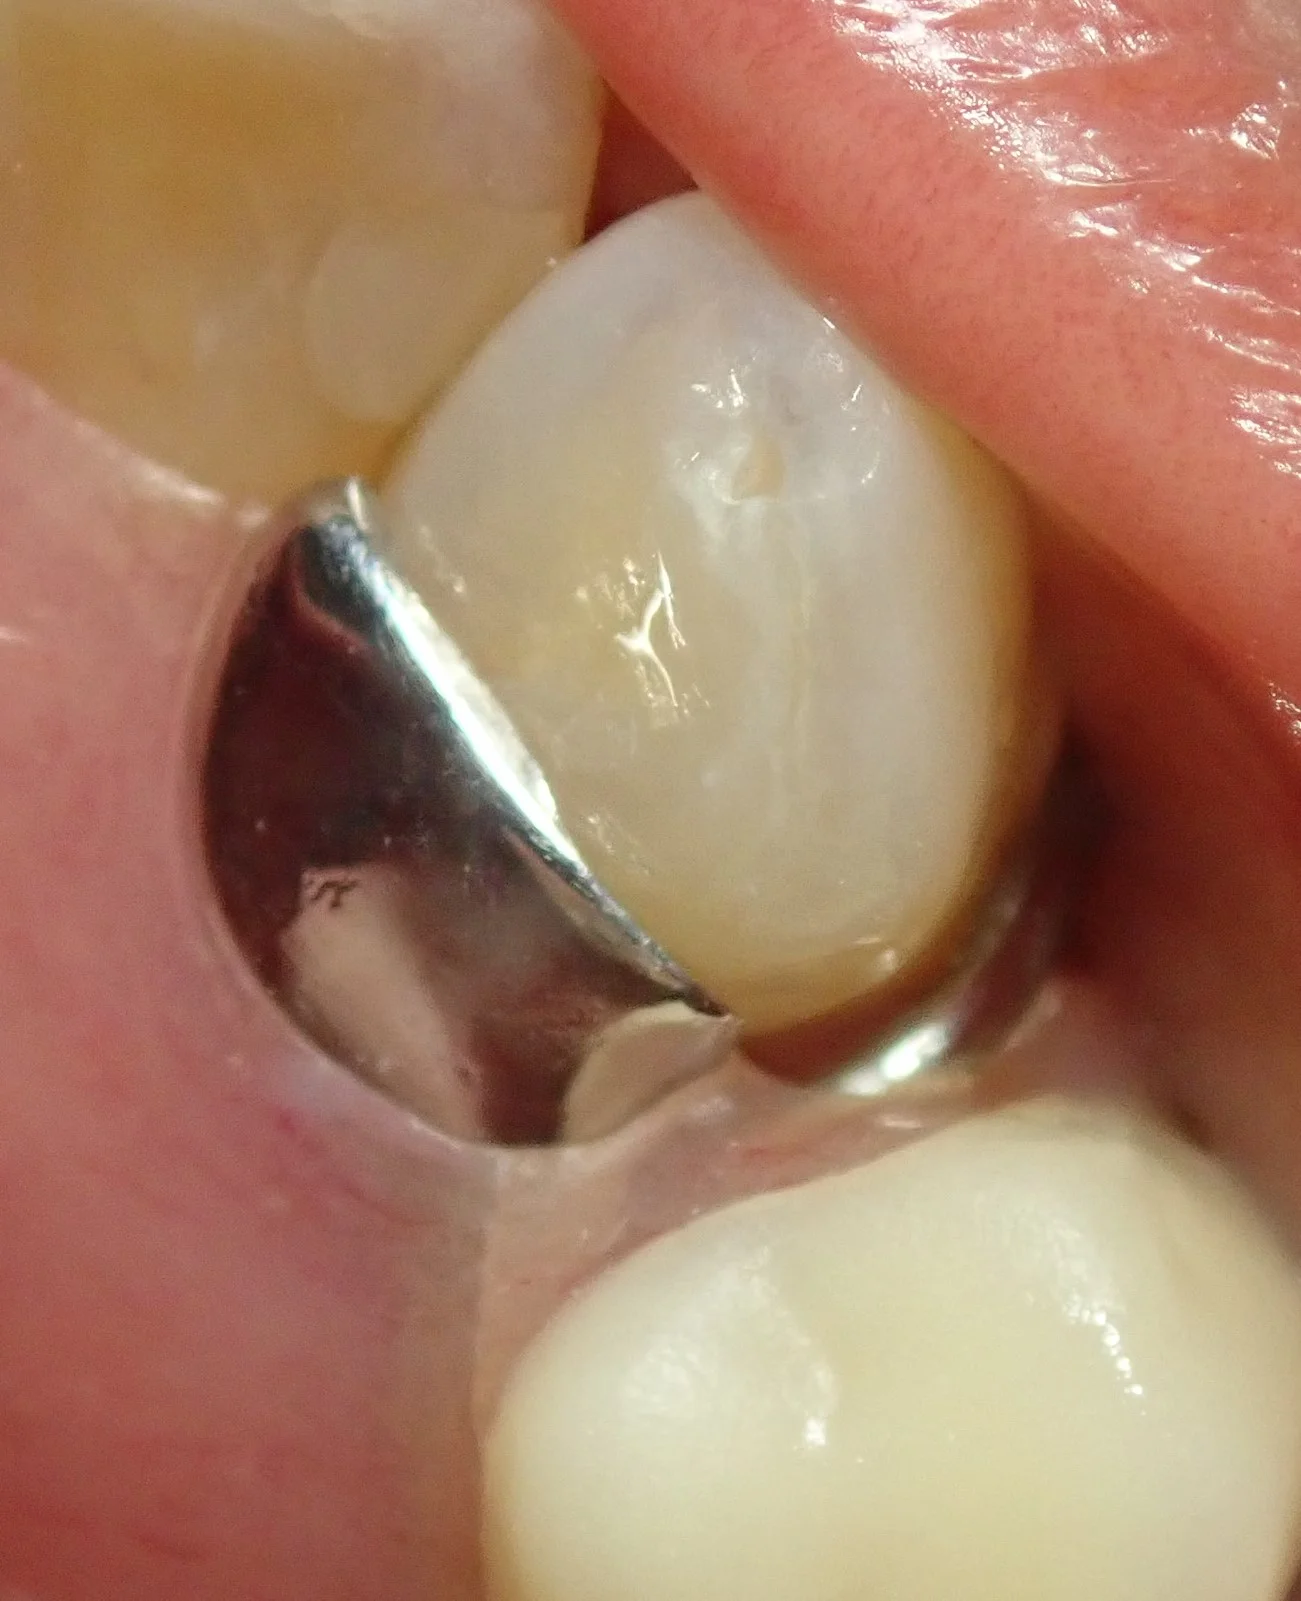

ある程度まで流動性の良い(フロアブル)コンポジットレジンで詰めておいて、最後一層を詰める時に流動性の悪い(ペースト)コンポジットレジンを乗せて~

テフロンテープをさっきインキしたシリコンに貼り付けて~

ぐっと歯に押し付けて形を整えると・・・

元の形態と同じ形態で詰めることが出来ます。

(ちなみに多少バリが出るのでそこは除去します)

で、そのまま研磨して、元の義歯を装着すると

こんな感じで、ぴったり隙間なく綺麗に詰めることが出来ますヽ(゚∀゚)ノ パッ☆

このテクニックの事をスタンプテクニックというのですが、

歯の形態が非常に残っている幼弱永久歯の虫歯の治療でも使えるテクニックになりますので、非常に便利です。